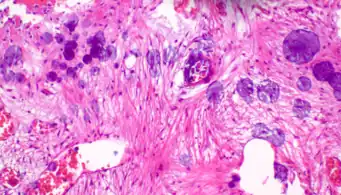

A crush artifact is an artificial elongation and distortion seen in histopathology and cytopathology studies, presumably because of iatrogenic compression of tissues. Distortion can be caused by the slightest compression of tissue and can provide difficulties in diagnosis.[2][3] It may cause chromatin to be squeezed out of nuclei.[4] Inflammatory and tumor cells are most susceptible to crush artifacts.[4]

4. 1 2 Chatterjee, Shailja (2014). "Artefacts in histopathology". Journal of Oral and Maxillofacial Pathology. 18 (4): S111–S116. doi:10.4103/0973-029X.141346. ISSN 0973-029X. PMC 4211218. PMID 25364159.

5. 1 2 3 Taqi, SyedAhmed; Sami, SyedAbdus; Sami, LateefBegum; Zaki, SyedAhmed (2018). "A review of artifacts in histopathology". Journal of Oral and Maxillofacial Pathology. 22 (2): 279. doi:10.4103/jomfp.JOMFP_125_15. ISSN 0973-029X. PMC 6097380. PMID 30158787.